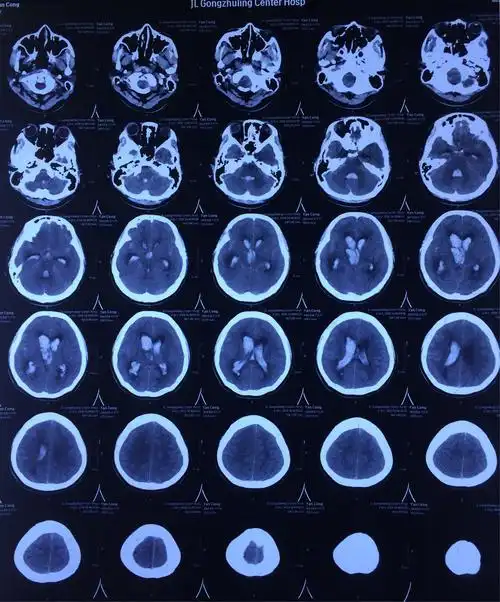

闫聪,女,16岁,右侧基底节出血破入脑室